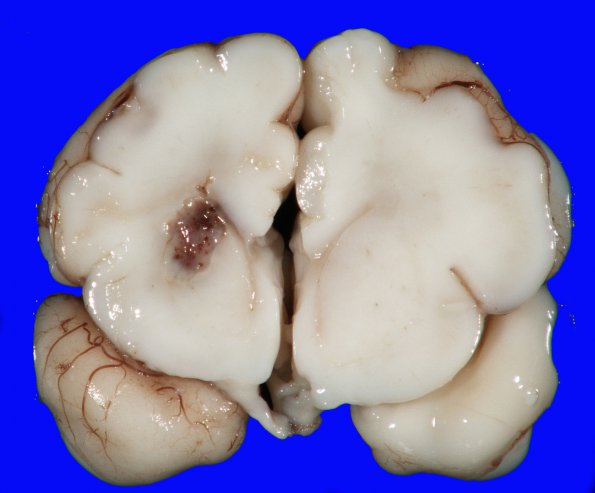

This immature brain shows an infarct in the left basal ganglia.